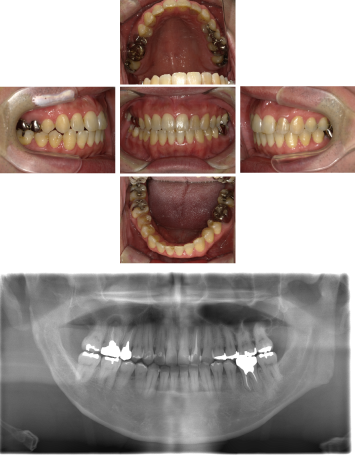

60代 女性 全顎 インプラント サイナスリフト等

| 年代・性別 | 60代・女性 |

| 主訴 | 上顎の入れ歯が割れた。リンゴやおかきを食べられるようになりたい。 |

| 部位 | 右上④3②・左上②3④5⑥のブリッジ |

| 治療期間 | 2年 |

| 費用 | ¥2,447,500(税込) |